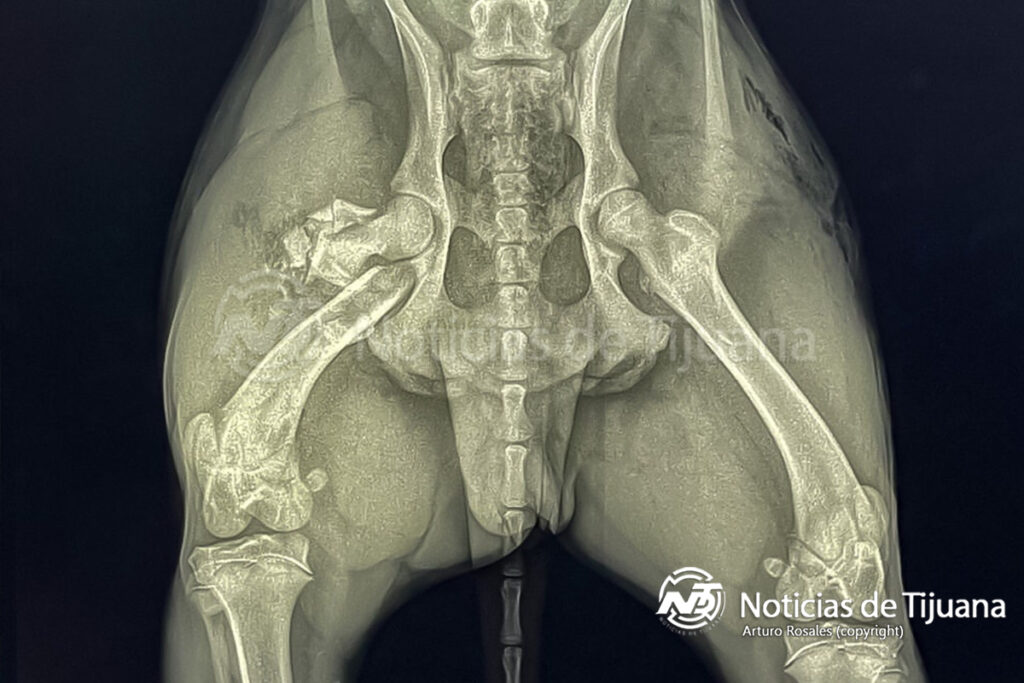

Durante la agresión, la perrita recibió un disparo que le provocó una fractura en el fémur. Paramédicos de Médica 2000 la trasladaron a la clínica veterinaria, donde permanece en estado grave a la espera de una cirugía.